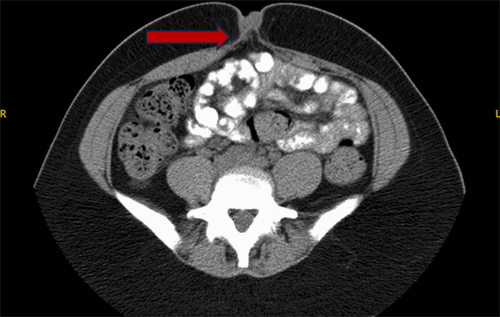

Figure 2. CT of Umbilical Hernia and Associated Nodule. Published with Permission

Axial view from a non-contrast CT scan of the abdomen and pelvis. The image shows a fat-containing umbilical hernia (arrow) with associated soft tissue nodularity at the umbilicus, findings which, in conjunction with the clinical history, were suspicious for an umbilical endometrioma

A 34-year-old G1P1 female presented with a two-year history of cyclical umbilical pain and bleeding, synchronous with her menses, associated with an umbilical hernia. Her past medical history was significant for anxiety, anemia, alopecia, and uterine fibroids; notably, she had no prior abdominal surgeries. The patient reported cyclical umbilical bleeding directly correlating with her menses. Her menstrual history was notable for polymenorrhea, with each cycle lasting seven days, and menorrhagia, evidenced by the need to change a menstrual cup every two hours on heavy flow days. She also reported a long-standing history of dysmenorrhea. Previous gynecological attempts to manage her menstrual symptoms with oral contraceptives and tranexamic acid were discontinued due to intolerable side effects. Upon presentation to the general surgery clinic, a non-contrast computed tomography (CT) scan of the abdomen and pelvis revealed a fat-containing umbilical hernia with associated nodularity at the umbilicus. At the time of this surgical consultation, the patient did not carry a prior diagnosis of endometriosis. She was subsequently referred to obstetrics and gynecology for further evaluation of her abnormal uterine bleeding and dysmenorrhea, where she was counseled on the probable diagnosis of an umbilical endometrioma and the high likelihood of concomitant pelvic endometriosis.